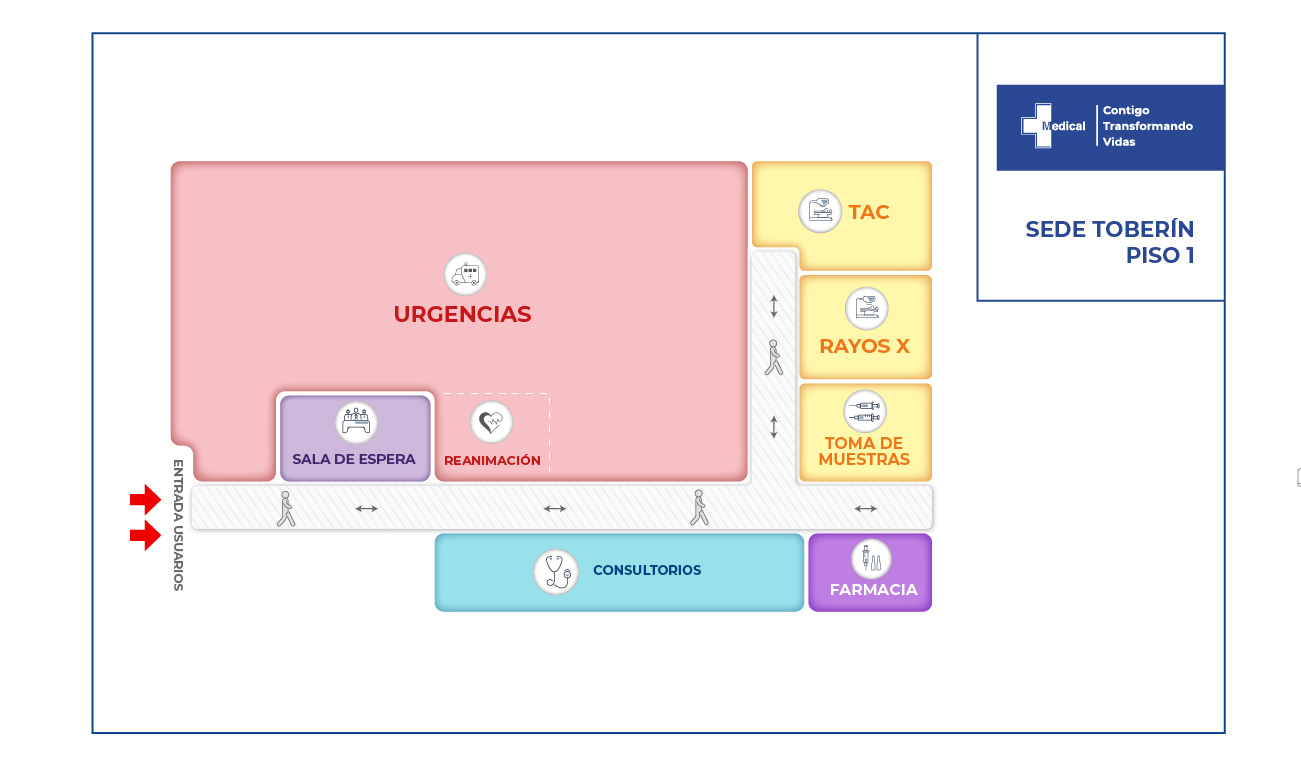

La condición de ingreso es realmente poco alentadora, sin embargo la oportunidad de los servicios, la eficiencia y eficacia que caracteriza a la clínica Medical SAS, ofrece al paciente y su familia todo un equipo interdisciplinario para la atención adecuada y secuencial para este tipo de traumas. Precedida por especialistas en cirugía general, neurocirugía, psicología, psiquiatría, servicios de apoyo terapéutico y radiológico, salas de cirugía, unidad de cuidados intensivos, rehabilitación física, clínica de heridas, entre otros.